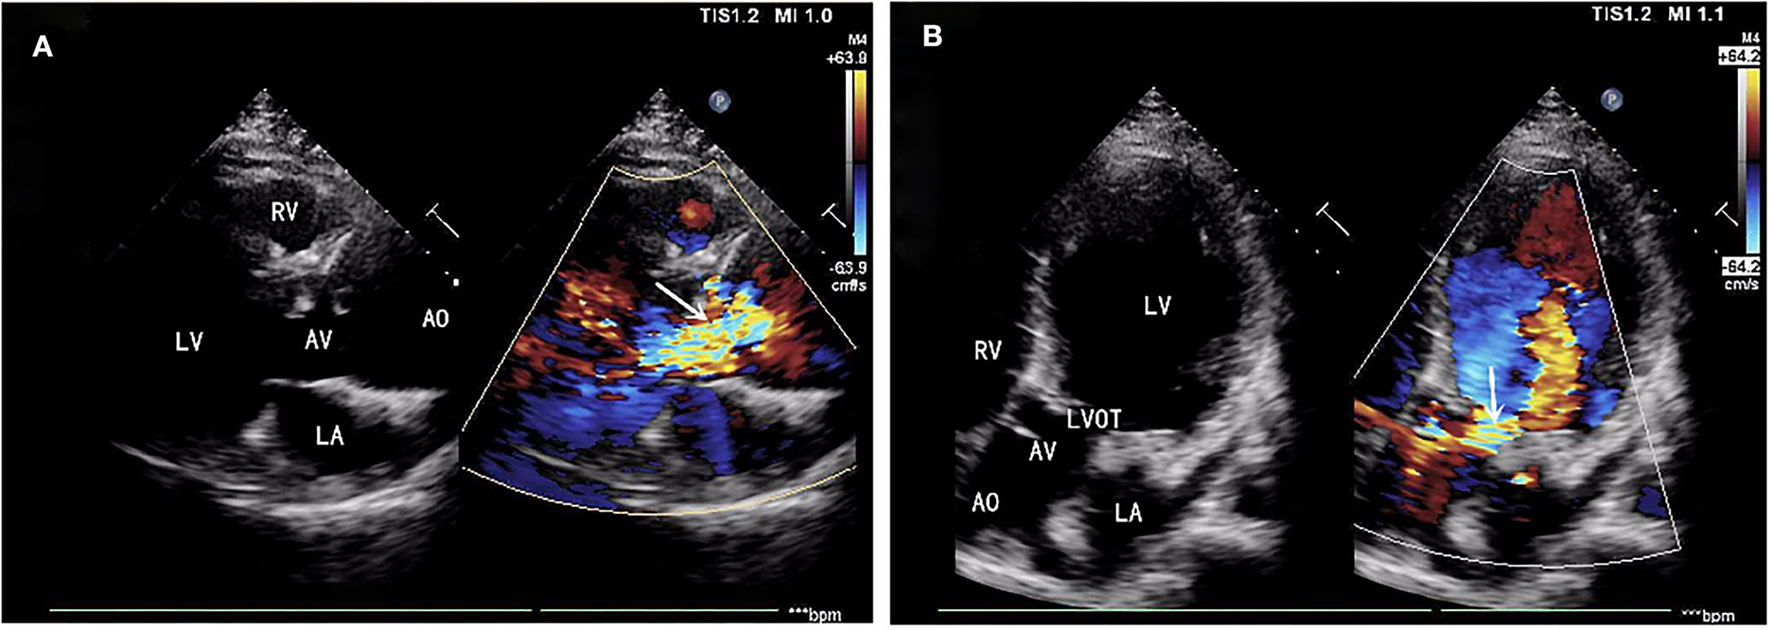

A 39-year-old male patient was admitted, complaining of persistent hemoptysis for 3 weeks. The patient was a typical TOF, not TOF of SD I type. Previously, he underwent radical surgery for tetralogy of Fallot, including relief of right ventricular outflow tract obstruction and repair of ventricular septal defect at 21. A diastolic murmur was found in the second left intercostal space of the sternum and other physical examinations were negative. Based on findings observed from cardiac echocardiography, it was diagnosed as dilatation for both sinotubular junction and ascending aorta (annulus, 3.17 cm; sinus, max. 5.82 cm; proximal ascending aorta, 4.14 cm) and aortic valve insufficiency complicated with severe AR (Figure 1A). The preoperative thoracic CT scan showed the diameter of the aortic root was 55.19 mm × 67.09 mm (Figure 2). Meanwhile, local obstruction of LVOT was also detected (Figure 1B), the gradients of LVOT obstruction was 23 mmHg. After clinical assessments, without any contradictions, this patient received the procedure including both David I plus repaired aortic valve procedure, combined with simultaneous reconstruction of LVOT.

Figure 1

(A) Aortic valve insufficiency complicated with severe aortic regurgitation (AR). (B) Local obstruction of left ventricular outflow tract (LVOT) (gradients of LVOT 23 mmHg). AR, aortic regurgitation; LVOT, left ventricular outflow tract.